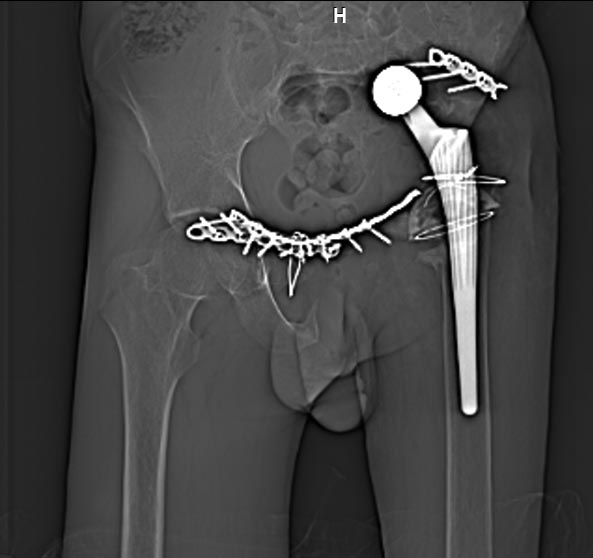

Мужчина 21 год, 2 года назад обнаружен эхиннокок костей таза, часть костей удалена сделано эндопротезирование и остеосинтез.Послеоперациооный период протекал гладко, через 6 месяцев упал, лечился консервативно, далее цепная реакция из проблем: гнойный остеомилит, свищи и лизис костей таза, на бак посеве эхинокок не обнаружен. Бедро не опорно, но больной предвигается на костылях. Картина маслом на рентгене и кт.об артродезировании думали, но диастаз большой, да и на фоне лизиса и остеопороза?????

Вложение не в текстовом формате было извлечено…

Имя     : xray.jpg

Тип     : image/jpg

Размер  : 43800 байтов

Описание: отсутствует

Url     : http://weborto.net:8080/pipermail/ortho/attachments/20121127/db0e4c1e/attachment-0004.jpg